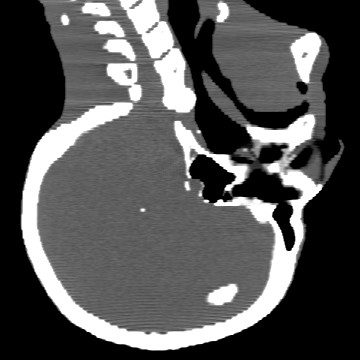

Cone-beam CT (CBCT) employs a flat-panel detector to achieve three-dimensional imaging with high spatial resolution. However, CBCT is susceptible to scatter during data acquisition, which introduces CT value bias and reduced tissue contrast in the reconstructed images, ultimately degrading diagnostic accuracy. To address this issue, we propose a deep learning-based scatter artifact correction method inspired by physical prior knowledge. Leveraging the fact that the observed point scatter probability density distribution exhibits rotational symmetry in the projection domain. The method uses Gaussian Radial Basis Functions (RBF) to model the point scatter function and embeds it into the Kolmogorov-Arnold Networks (KAN) layer, which provides efficient nonlinear mapping capabilities for learning high-dimensional scatter features. By incorporating the physical characteristics of the scattered photon distribution together with the complex function mapping capacity of KAN, the model improves its ability to accurately represent scatter. The effectiveness of the method is validated through both synthetic and real-scan experiments. Experimental results show that the model can effectively correct the scatter artifacts in the reconstructed images and is superior to the current methods in terms of quantitative metrics.